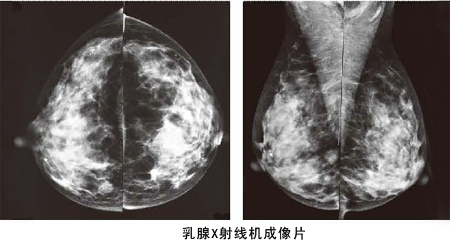

鉬靶和彩超是乳腺檢查中極常用的兩種檢查。那什么人適合做鉬鈀檢查呢?35歲以下醫(yī)生一般不推薦做乳腺鉬靶檢查,只需做彩超檢查即可。如超聲懷疑有問題,可再做鉬靶檢查。而鉬靶檢查是x射線檢查,所以我們女性懷孕前后建議不要做。40歲以上女性,因?yàn)檫M(jìn)入到乳腺癌高發(fā)年齡段,因此建議每年做一次鉬靶檢查。

做乳腺鉬靶檢查有什么優(yōu)勢?

乳腺鉬靶檢查是針對彩超檢查不能確定的腫塊,或是是不能發(fā)現(xiàn)的腫塊進(jìn)行檢查, 它的特點(diǎn)是可以檢測出醫(yī)生觸摸不到的乳腺腫塊,特別是對于大乳房和脂肪型乳房,其診斷性可高達(dá)95%,對于以少許微小鈣化為獨(dú)有表現(xiàn)的T0期乳腺癌,也只有憑借軟X線檢查才能被早期發(fā)現(xiàn)和診斷。

乳腺鉬靶檢查系統(tǒng)是一種低劑量乳腺X光拍攝乳房的技術(shù),它能清晰顯示乳腺各層組織,可以發(fā)現(xiàn)乳腺增生,各種良惡性腫廇以及乳腺組織結(jié)構(gòu)紊亂,可觀察到小于0.1毫米的微小鈣化點(diǎn)及鈣化簇,是早期發(fā)現(xiàn),診斷乳腺癌的極有效和可靠的方式,尤其對于臨床不可能及的,以微小鈣化簇為獨(dú)有表現(xiàn)的早期乳腺癌具有特征性的診斷意義。

乳腺鉬靶檢查系統(tǒng)具有成像清晰、檢查操作方便快捷、輻射量小等特點(diǎn),該儀器檢查診斷可準(zhǔn)確發(fā)現(xiàn)乳腺增生、病變、包塊、鈣化的形狀、大小、密度、性質(zhì)等。對于彩超無法辨別的乳腺病變鈣化點(diǎn)進(jìn)行準(zhǔn)確判斷與鑒別。

另外鉬靶照相對于年輕女性乳腺有一定的損傷,因此檢查不宜過勤,40歲以上的女性一年檢查一次為宜。希望小編的這篇什么人適合做鉬鈀檢查以及做乳腺鉬靶檢查有什么優(yōu)勢的小文章能幫到大家。